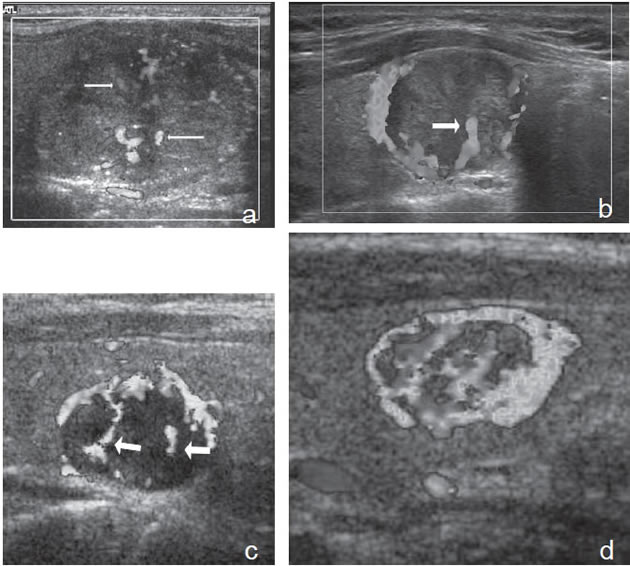

7. Invasión local y adenopatías

La extensión de la masa fuera de la cápsula, la infiltración de la tráquea o de los músculos pretiroideos es muy sugerente de malignidad (Figura 15a). Asímismo, la presencia de adenopatías con características típicas, debe hacer sospechar que el nódulo tiroideo es maligno. Los cánceres papilares de la tiroides son propensos a dar metástasis precozmente a los linfonodos cervicales y hasta la mitad de todos los pacientes pueden presentar adenopatías concomitantes. En 15% de los pacientes, el único signo de un cáncer tiroideo papilar oculto puede ser la detección de adenopatías. La mayoría de las metástasis ocurren ipsilateralmente al tumor primario en los grupos III y IV de la cadena yugular interna y del grupo VI del compartimiento central. En la ecografía, los linfonodos metastáticos pueden tener una forma redondeada o globular, una arquitectura con elementos sólidos o quísticos, con o sin microcalcificaciones y pérdida del hilio (Figura 15b y c). El “Doppler color” puede demostrar vasos capsulares de distribución caótica en reemplazo de los vasos hiliares normales (Figura 15d). Las adenopatías hiperecogénicas son sospechosas de cáncer papilar (Figura 16a). Los linfonodos normales en algunos grupos como el VI y el VII no se ven ecograficamente, de manera que si se hacen visibles, en el mismo lado del tumor, independiente del tamaño que tengan hay que considerarlos como adenopatías metastásicas (Figura 16b)

Figura 15. a) Cáncer papilar sólido de bordes lobulados (flechas) que muestra una gruesa calcificación central (flecha abierta) y múltiples

microcalcificaciones; b) Adenopatía cervical del grupo IV del mismo paciente (figura 15 a), hiperecogénica, con elementos quísticos (flecha

blanca) y microcalcificaciones agrupadas (flechas negras), típica de cáncer papilar; c) Adenopatías de grupo IV de un cáncer papilar, de

forma redondeada, hiperecogénicas, con pérdida del hilio, una anterior a la arteria carótida común (flecha) y otra lateral a la vena yugular

interna (flecha abierta); d) Corte sagital de la adenopatía lateral de la imagen 15 c), que en “doppler color” muestra vascularización patológica

y pérdida del hilio.

La apariencia ecográfica de los linfonodos metastásicos puede ser distinta a las del tumor primario y mostrar elementos quísticos y microcalcificaciones en mayor proporción que en el primario. En pacientes más jóvenes, las adenopatías puramente quísticas son relativamente comunes y cuando son solitarias pueden simular un quiste branquial o un quiste del conducto tirogloso.